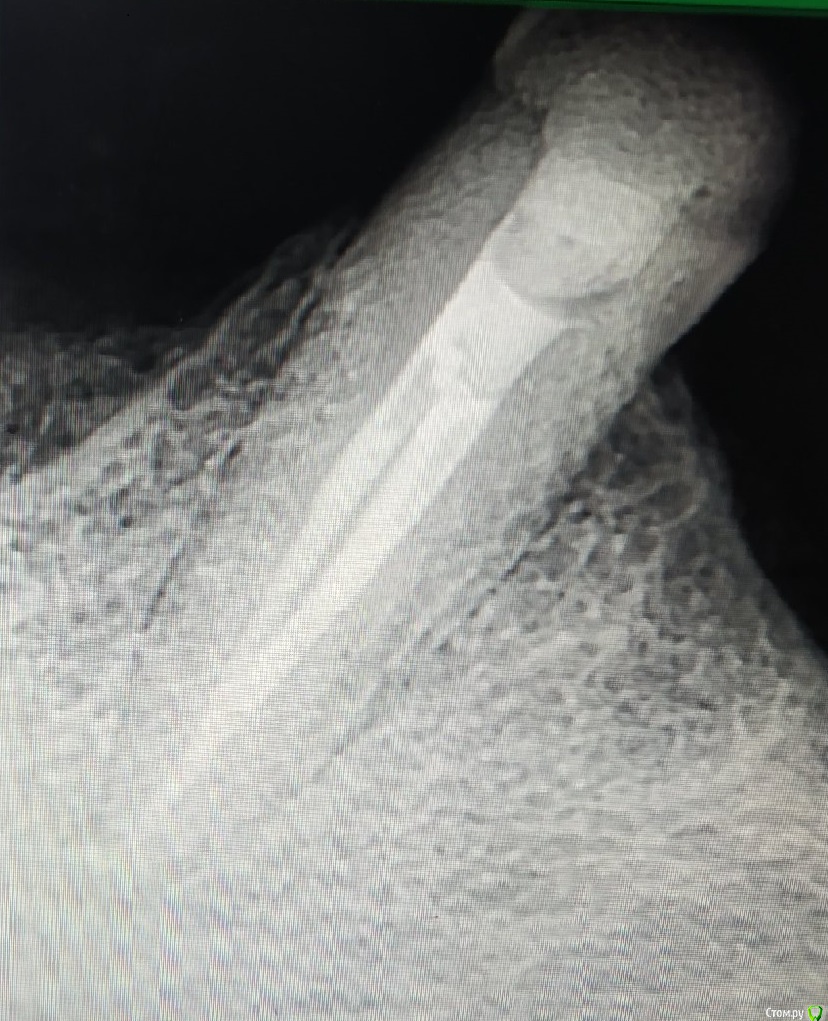

4.6 - острый пульпит. В дистальном 25.04, в медиальных 20.02. Не смог обработать до большего, да и не увидел в этом смысла. В дистальном я силер не выводил, он сам))